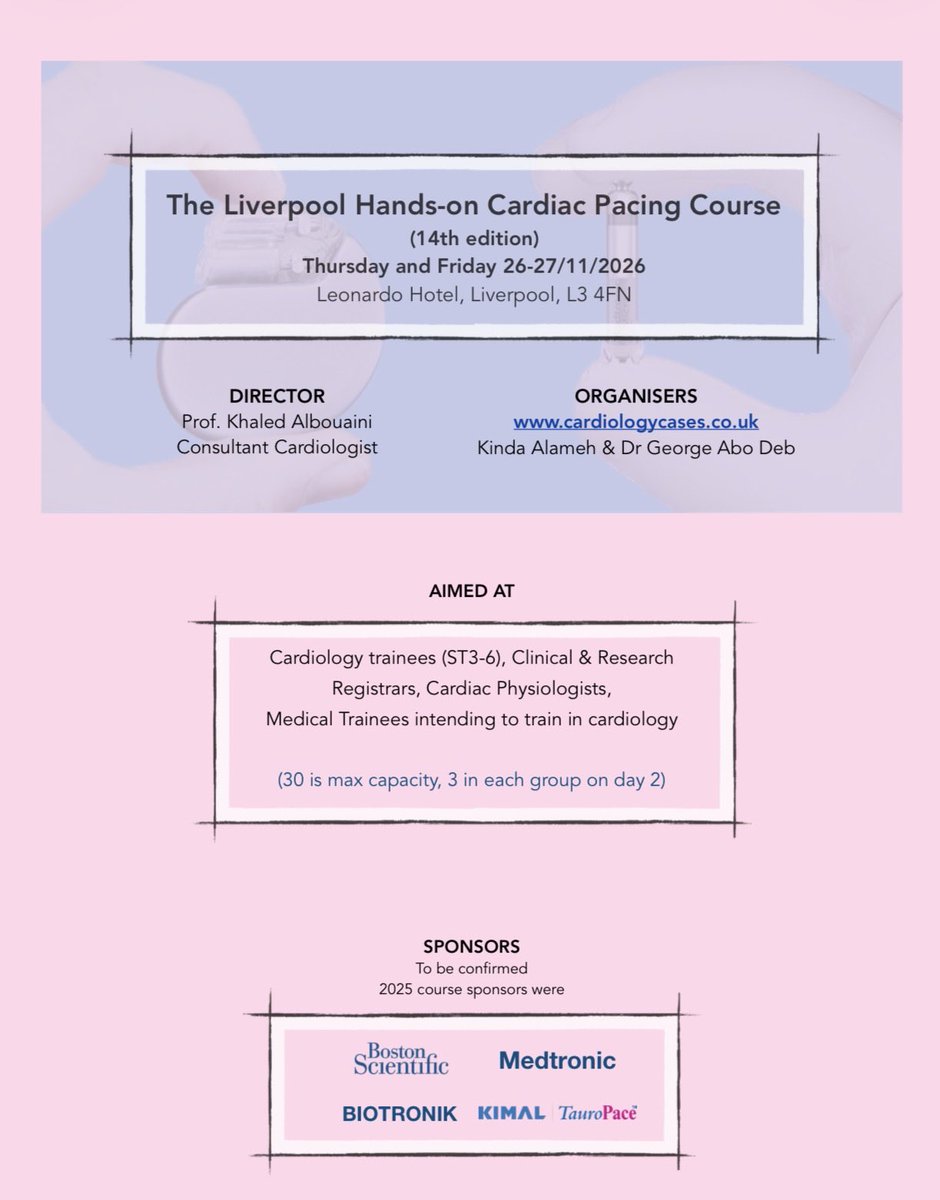

The 14th edition of our National Hands-on Cardiac Pacing Course, scheduled for Thursday -Friday 26-27/11/26. See the overwhelmingly positive feedback (pages 5-8) on PDF flyer: cardiologycases.co.uk. #MedTwitter @BritishCardioSo @TheBJCA @BHRSociety #CardioEd #CardioTwitter